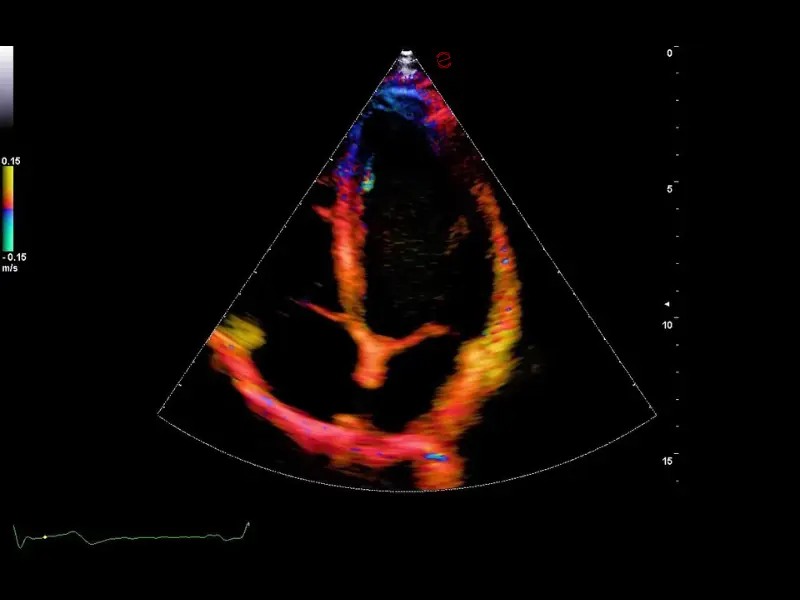

The MyLab™C30 compact ultrasound machine is specifically designed to meet the demands of everyday clinical practice for fast ultrasound access, versatility of use, and space constraints. All this has been achieved without compromising image quality and ultrasound performance. By sharing advanced imaging technologies and transducers with our high-end systems, the MyLab™C30 delivers high quality images and clinical information in a truly compact ultrasound device.

Elevated performance for enhanced diagnostic insights

Featuring the ClearWave Architecture, which combines Esaote’s advanced XBeamforming and XSmart Postprocessing technologies, the MyLab™C30 incorporates state-of-the-art imaging technologies to set a new standard for image quality, giving professionals diagnostic confidence wherever they need it. Maximize the performance of the MyLab™C30 with its wide range of probes for all clinical needs, from daily routine to the most advanced expectations. Equipped with a wide range of advanced features and an accelerated workflow powered by Artificial Intelligence, the MyLab™C30 is your portable ultrasound device that knows no boundaries.

Rely on experience: CAmed Medical Systems is your strong partner in medical technology